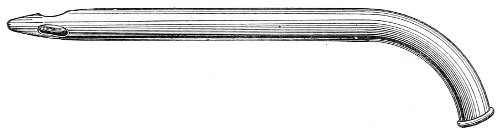

The uterine sound is an instrument by which the length of the uterine cavity may be determined (Fig. 15). The sound, which is a large surgical probe, somewhat curved to adapt itself to the normal shape of the uterine axis, is made of pliable metal, so that the curvature may be changed readily to suit any case. The sound is graduated, and at a position of 2½ inches from the tip is a small elevation marking the length of the normal uterine cavity.

Fig. 15.—Uterine sound.

The uterine sound was at one time used a great deal to determine the length and direction of the uterus, and 35 perhaps to assist in determining the character of the uterine contents or of the endometrium. With our present methods of examination, however, the sound is of but little if any use. The size and direction of the uterus can in nearly all cases be determined by bimanual examination. The use of the uterine sound is by no means free from danger. Many cases of septic endometritis and salpingitis have been caused by it, and the physician has often unintentionally committed an abortion by passing the sound in a pregnant woman. The uterine sound should never be used in a routine way. It should never be used unless one expects to determine with it something that cannot be determined by simpler methods of examination.

The most thorough aseptic precautions should be observed when the sound is introduced. The vulva, vagina, and cervix should be cleaned and the sound should be sterilized. The sound should never be introduced if there is any suspicion of pregnancy.